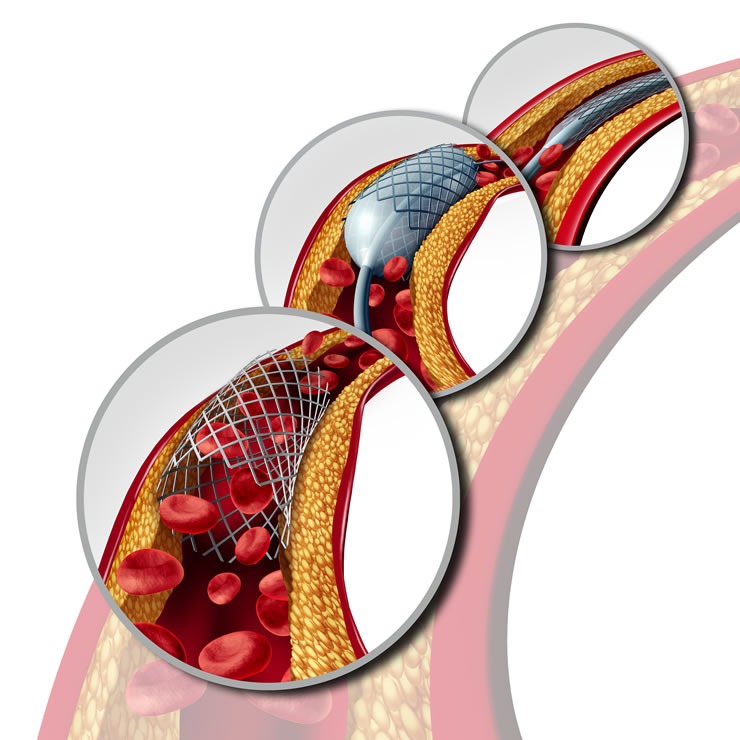

Αγγειοπλαστική

Είναι μία ελάχιστα επεμβατική θεραπευτική μέθοδος μέσω της κερκιδικής ή της μηριαίας αρτηρίας. Η αγγειοπλαστική πραγματοποιείται με μπαλόνια, stent ή συνηθέστερα με τον συνδυασμό και των δύο. Μέσω ενός καθετήρα αγγειοπλαστικής προωθείται αρχικώς ένα οδηγό σύρμα, το οποίο λειτουργεί ώς το κατευθυντήριο μέσο, μέσω του οποίου προωθούνται οι συσκευές (μπαλόνια, stents, συσκευές αθηρεκτομής, συσκευές θρομβο-αναρρόφησης, IVUS, OCT). Αφού τοποθετηθεί το μπαλόνι ή το stent στην περιοχή στόχο, εκπτύσσονται μέσω θετικής πίεσης ολοκληρώνοντας την παρέμβαση.